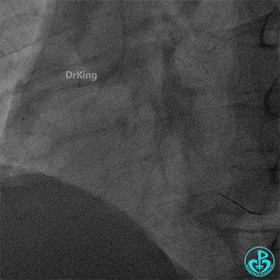

血栓移位至后三叉,冠脉血栓抽吸导管再次反复抽吸无果,送刺破球囊至RCA病变处再次冠脉内注射重组人TNK组织型纤溶酶原激活剂8mg,等待10分钟后造影示后三叉的血栓完全消失,前向血流TIMI 3级。

右冠脉近段植入1枚4.0×24mm支架,后扩张后造影示前向血流TIMI 3级。